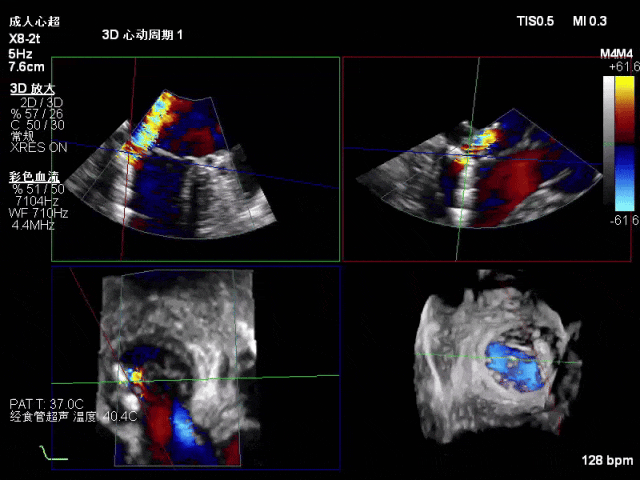

术中超声(关键步骤)

术前心超

退行性二尖瓣反流(DMR),P1/P2交界脱垂连枷(脱垂范围7mm,连枷间距4mm)

新分型:AAA型,MR 4+,VC:4×7mm

A1.5:20mm,P1.5:10mm,AP:30mm,MVA约3.8cm²